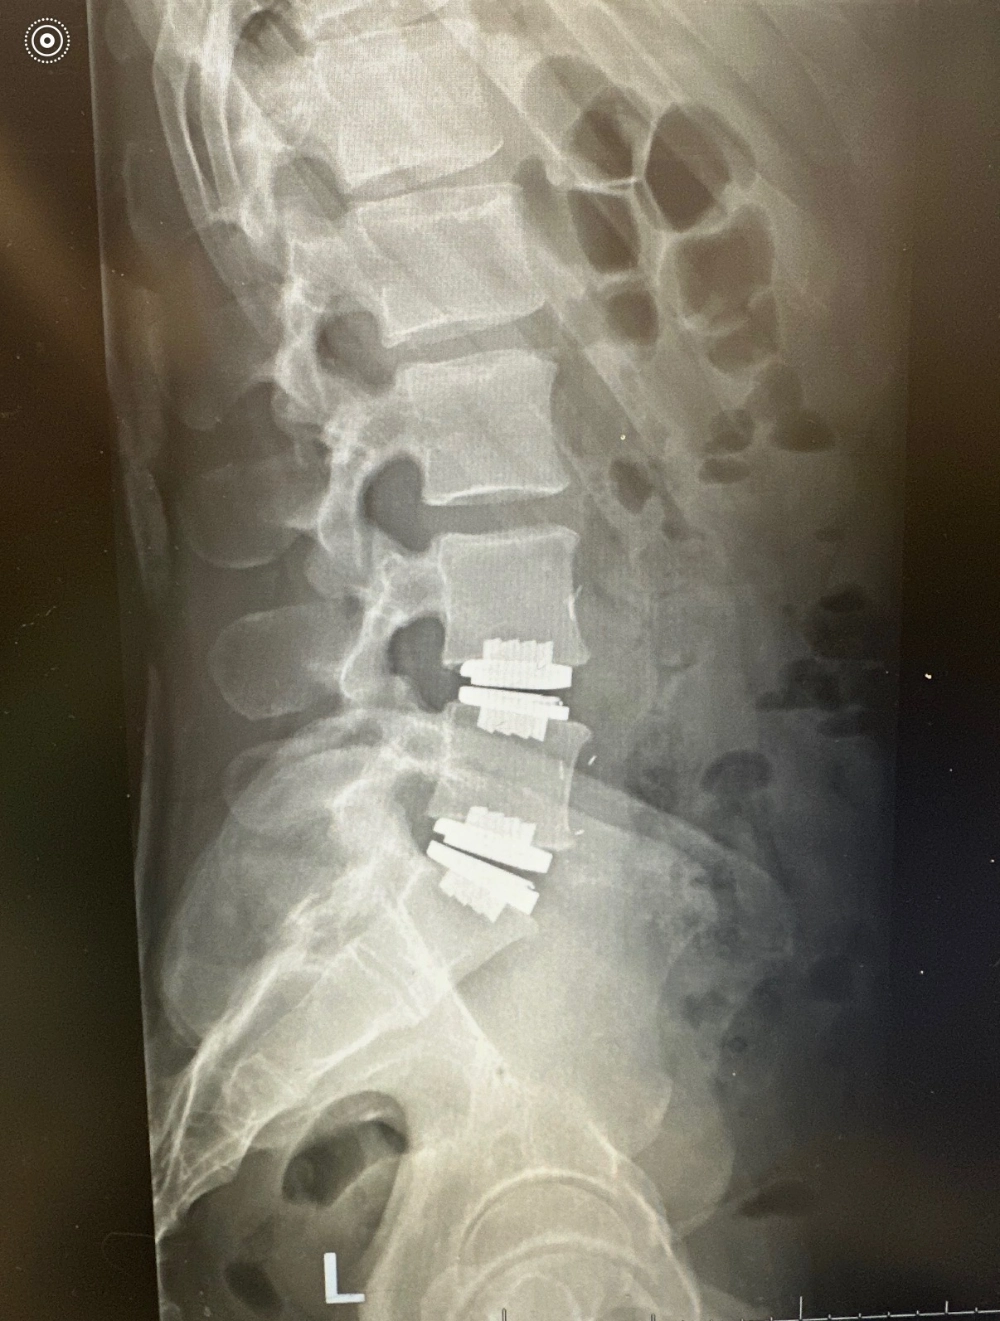

Lumbar disc replacement is a motion-preserving surgical procedure used to treat painful, damaged discs in the lower back. Instead of removing the disc and fusing the vertebrae together, the damanged disc is replaced with an artificial disc implant designed to mimic the natural movement and cushioning of a healthy disc.

This artificial disc restores normal disc height, relieves pressure on nearby nerves, and allows the spine to continue bending, rotating, and absorbing impact naturally. Unlike fusion, which permanently locks two bones together, lumbar disc replacement maintains motion and helps reduce stress on surrounding spinal levels.

- An artificial disc implant is precisely positioned using advanced imaging